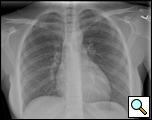

Patient is a 29 year old female, who was diagnosed with a pericardial cyst when she was 17 years old during a work-up of asthma. Recently, the patient presented with a persistent cough, and a repeat CT scan revealed increase in size of the cyst to approximately 6x6cm (Figures 1 and 2). Her past medical history was significant for Wolff-Parkinson-White syndrome. On examination no abnormalities were found. Since the cyst was enlarging, causing significant anxiety, and possibly contributing to her persistent cough, resection was recommended. Her cardiologists felt that her WPW Syndrome was not a contraindication to surgery.

| Figure 1. Preoperative Chest x-ray. | Figure 2. Chest CT scan showing right cardiophrenic pericardial cyst. |